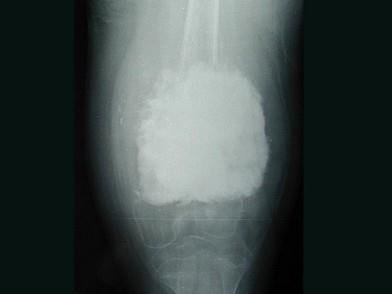

问题 女,10岁,左大腿疼痛,夜间加重,肿胀明显,请结合影像图像,最可能的诊断是 ( )

选项 A、骨化性肌炎 B、以上都不正确 C、化脓性骨髓炎 D、骨肉瘤 E、成骨性骨转移

答案 D